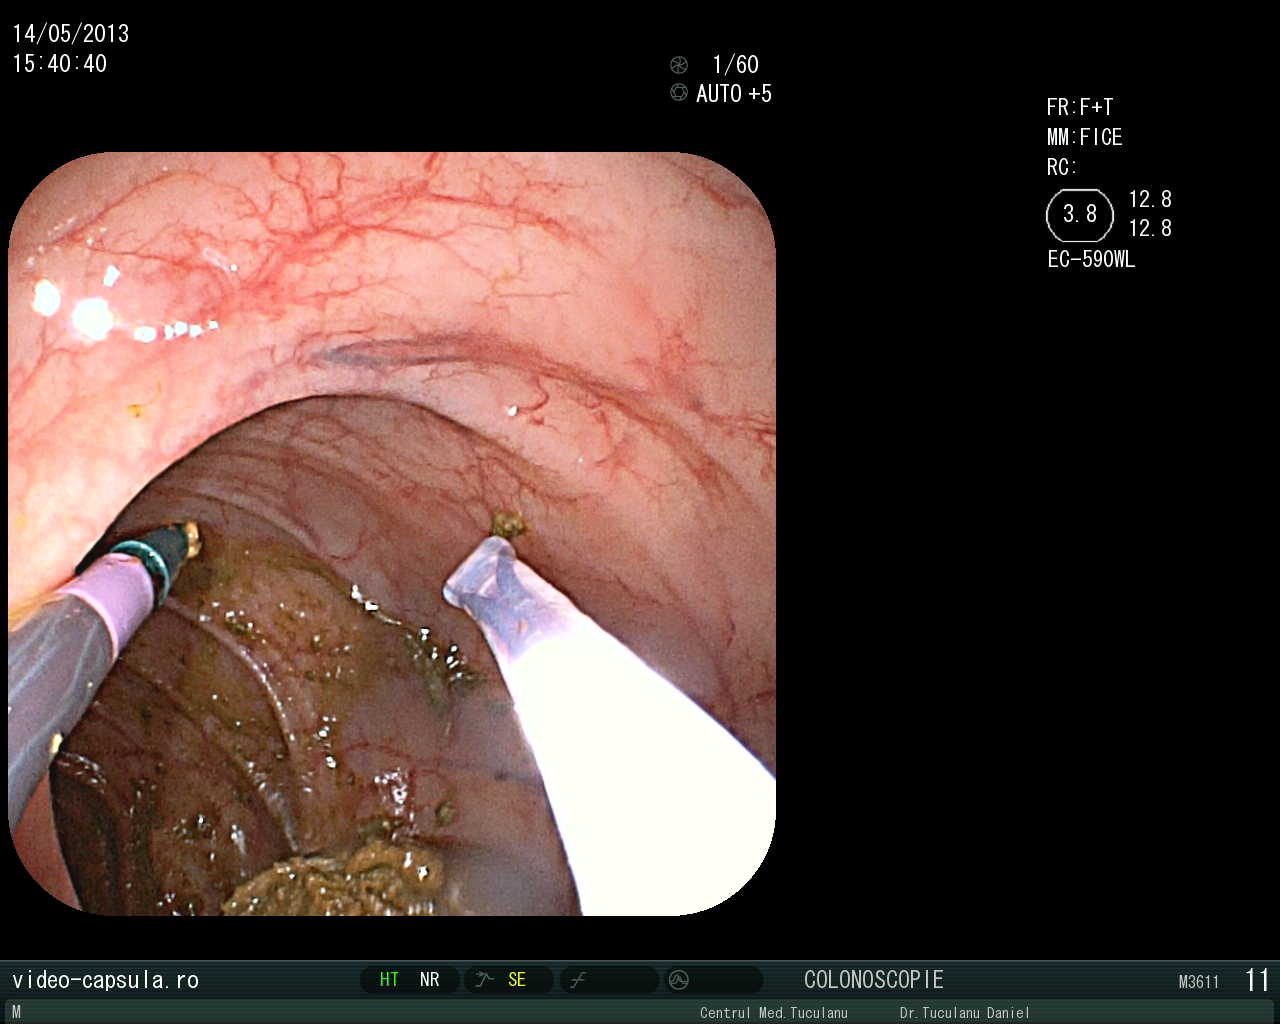

• Stent în cancer sigmoidian inoperabil •

Tratament endoscopic (nechirurgical) pentru evitarea operației paleative sau anusului contra naturii în cancerul colo-rectal avansat

Montarea de stent-uri (proteze) esofagiene, duodenale sau colo-rectale în stenoze canceroase sau necanceroase